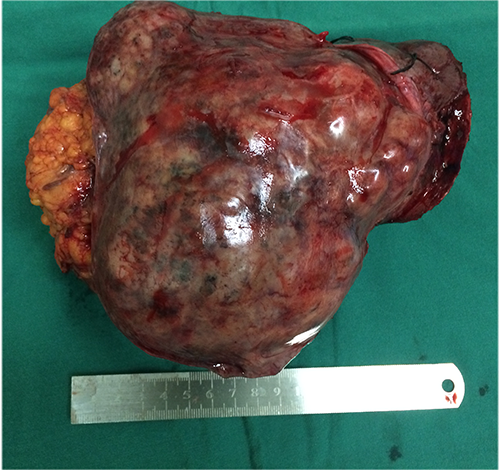

左肝癌--左半肝切除